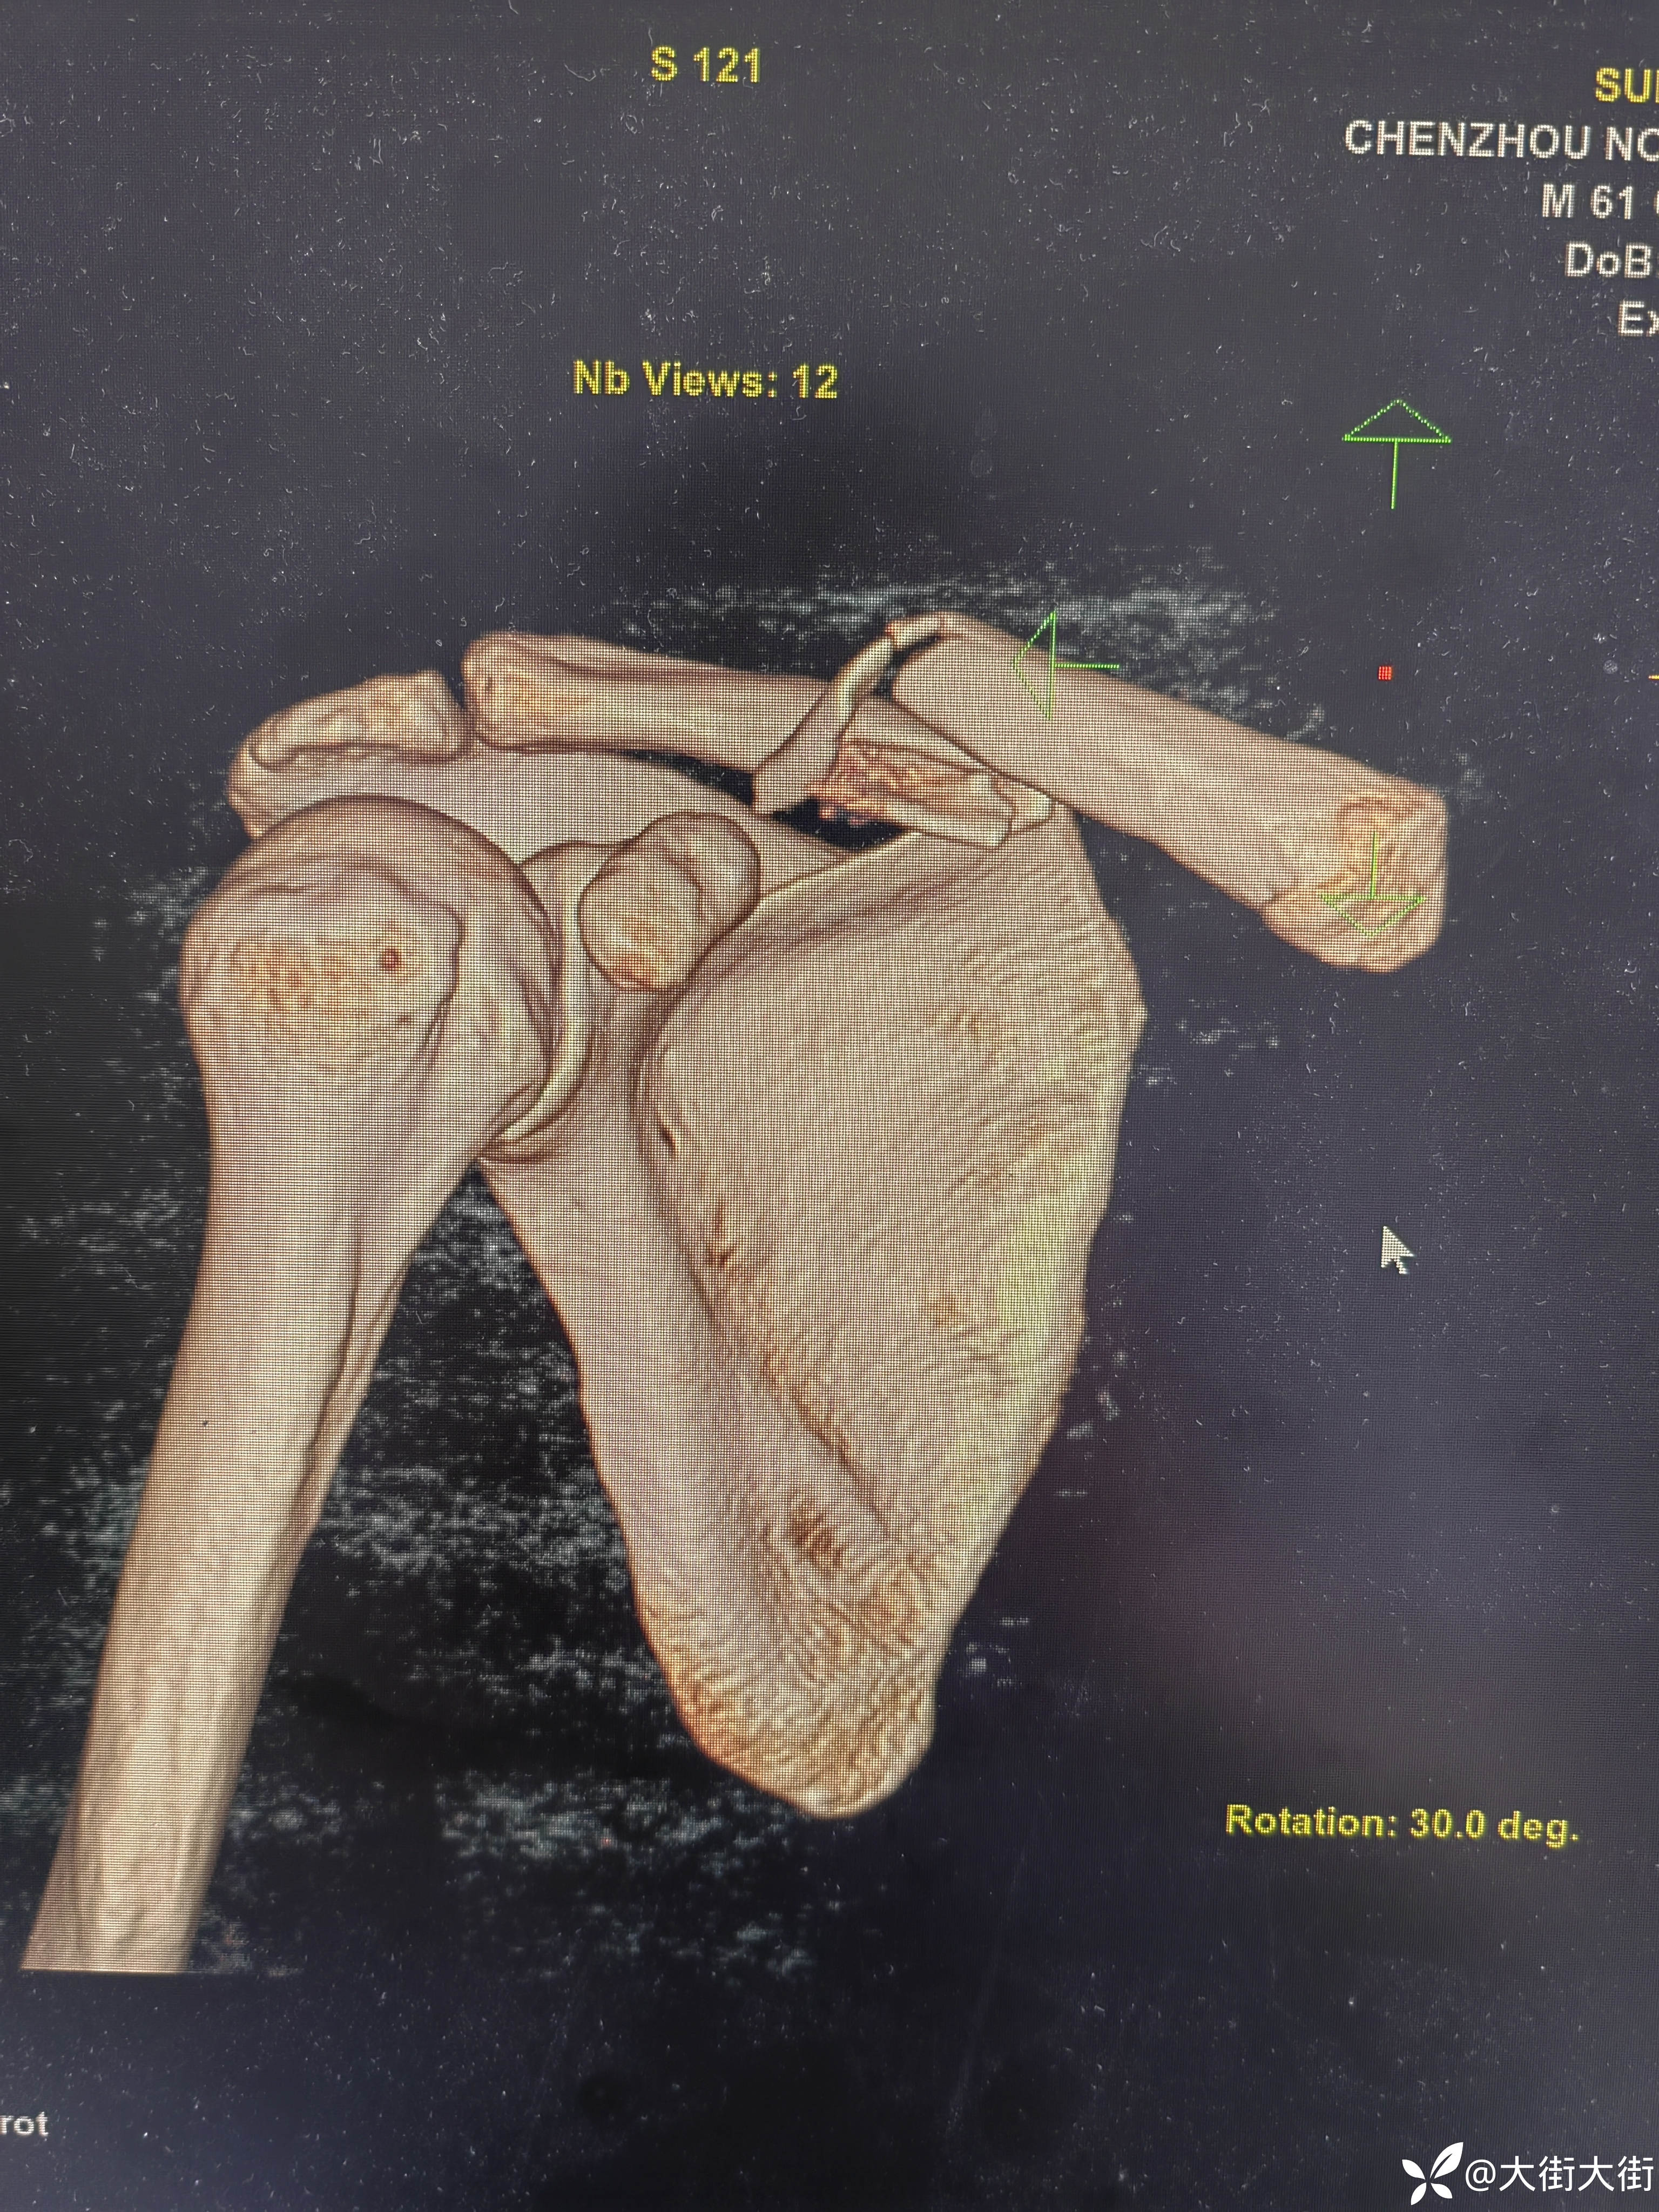

【患者信息】:男,61岁

【主诉】:外伤致右肩部疼痛,活动受限3天。

【临床诊断】:

第一次做,比想象中要难点,第一感觉就是明显的视野受限。板子放的不是很完美,切口位置没把握好,下次用马克笔画一下。各位老师轻点喷。